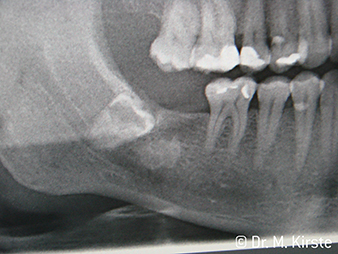

Erstmals kombinieren die Übertragungsinstrumente WS-91 und WS-91 L G die Vorteile von chirurgischen Hand- und Winkelstücken (Abbildung 1). Der auf der Vorderseite erweiterte Winkel zwischen Griffbereich und Bohrerachse erlaubt einen guten Zugang sowohl von bukkal als auch von okklusal über die Zahnreihe (Abbildung 4). Verlagerte Zähne lassen sich bequem trennen (Abbildung 6 und 7). Zudem überblickt der Behandler oder die Behandlerin das Operationsfeld deutlich besser als mit bisher verfügbaren Instrumenten. Dazu Dr. Mario Kirste aus Frankfurt/Oder: „Wenn ich den Winkelstückkopf leicht drehe, kann ich im retromolaren Bereich besonders sicher und schnell arbeiten. Das Instrument hat das Potenzial, die gegensätzlichen Lager der Handstück- und Winkelstückanwender zu versöhnen.“ (Abbildung 2 - 5)

Eine weitere Indikation der Winkelstücke WS-91 / WS-91 L G ist die Wurzelspitzenresektion. Auch bei Oberkiefer-Molaren und kleiner Mundöffnung sorgt die ausgefeilte Ergonomie für gute Sicht. Beim WS-91 L G kommt eine Mini-LED+ hinzu, die das Operationsgebiet tageshell ausleuchtet. Dr. Kirste: „Die neuen Winkelstücke sind eine wirklich gelungene Gradwanderung. Diese wunderbare technische Leistung von W&H erweitert meinen Blickwinkel und meine Möglichkeiten in der täglichen Chirurgie.“